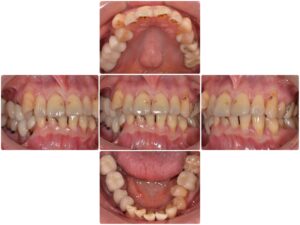

主訴・術前

むし歯とインプラントの治療をしたい

診断名 |

審美障害 |

年齢 |

50代女性 |

治療方法 |

インプラント治療 セラミック治療 矯正治療 歯周治療 |

抜歯部位 |

左上5.7 右下4.6 左下6 |

治療期間 |

1年8ヵ月 |